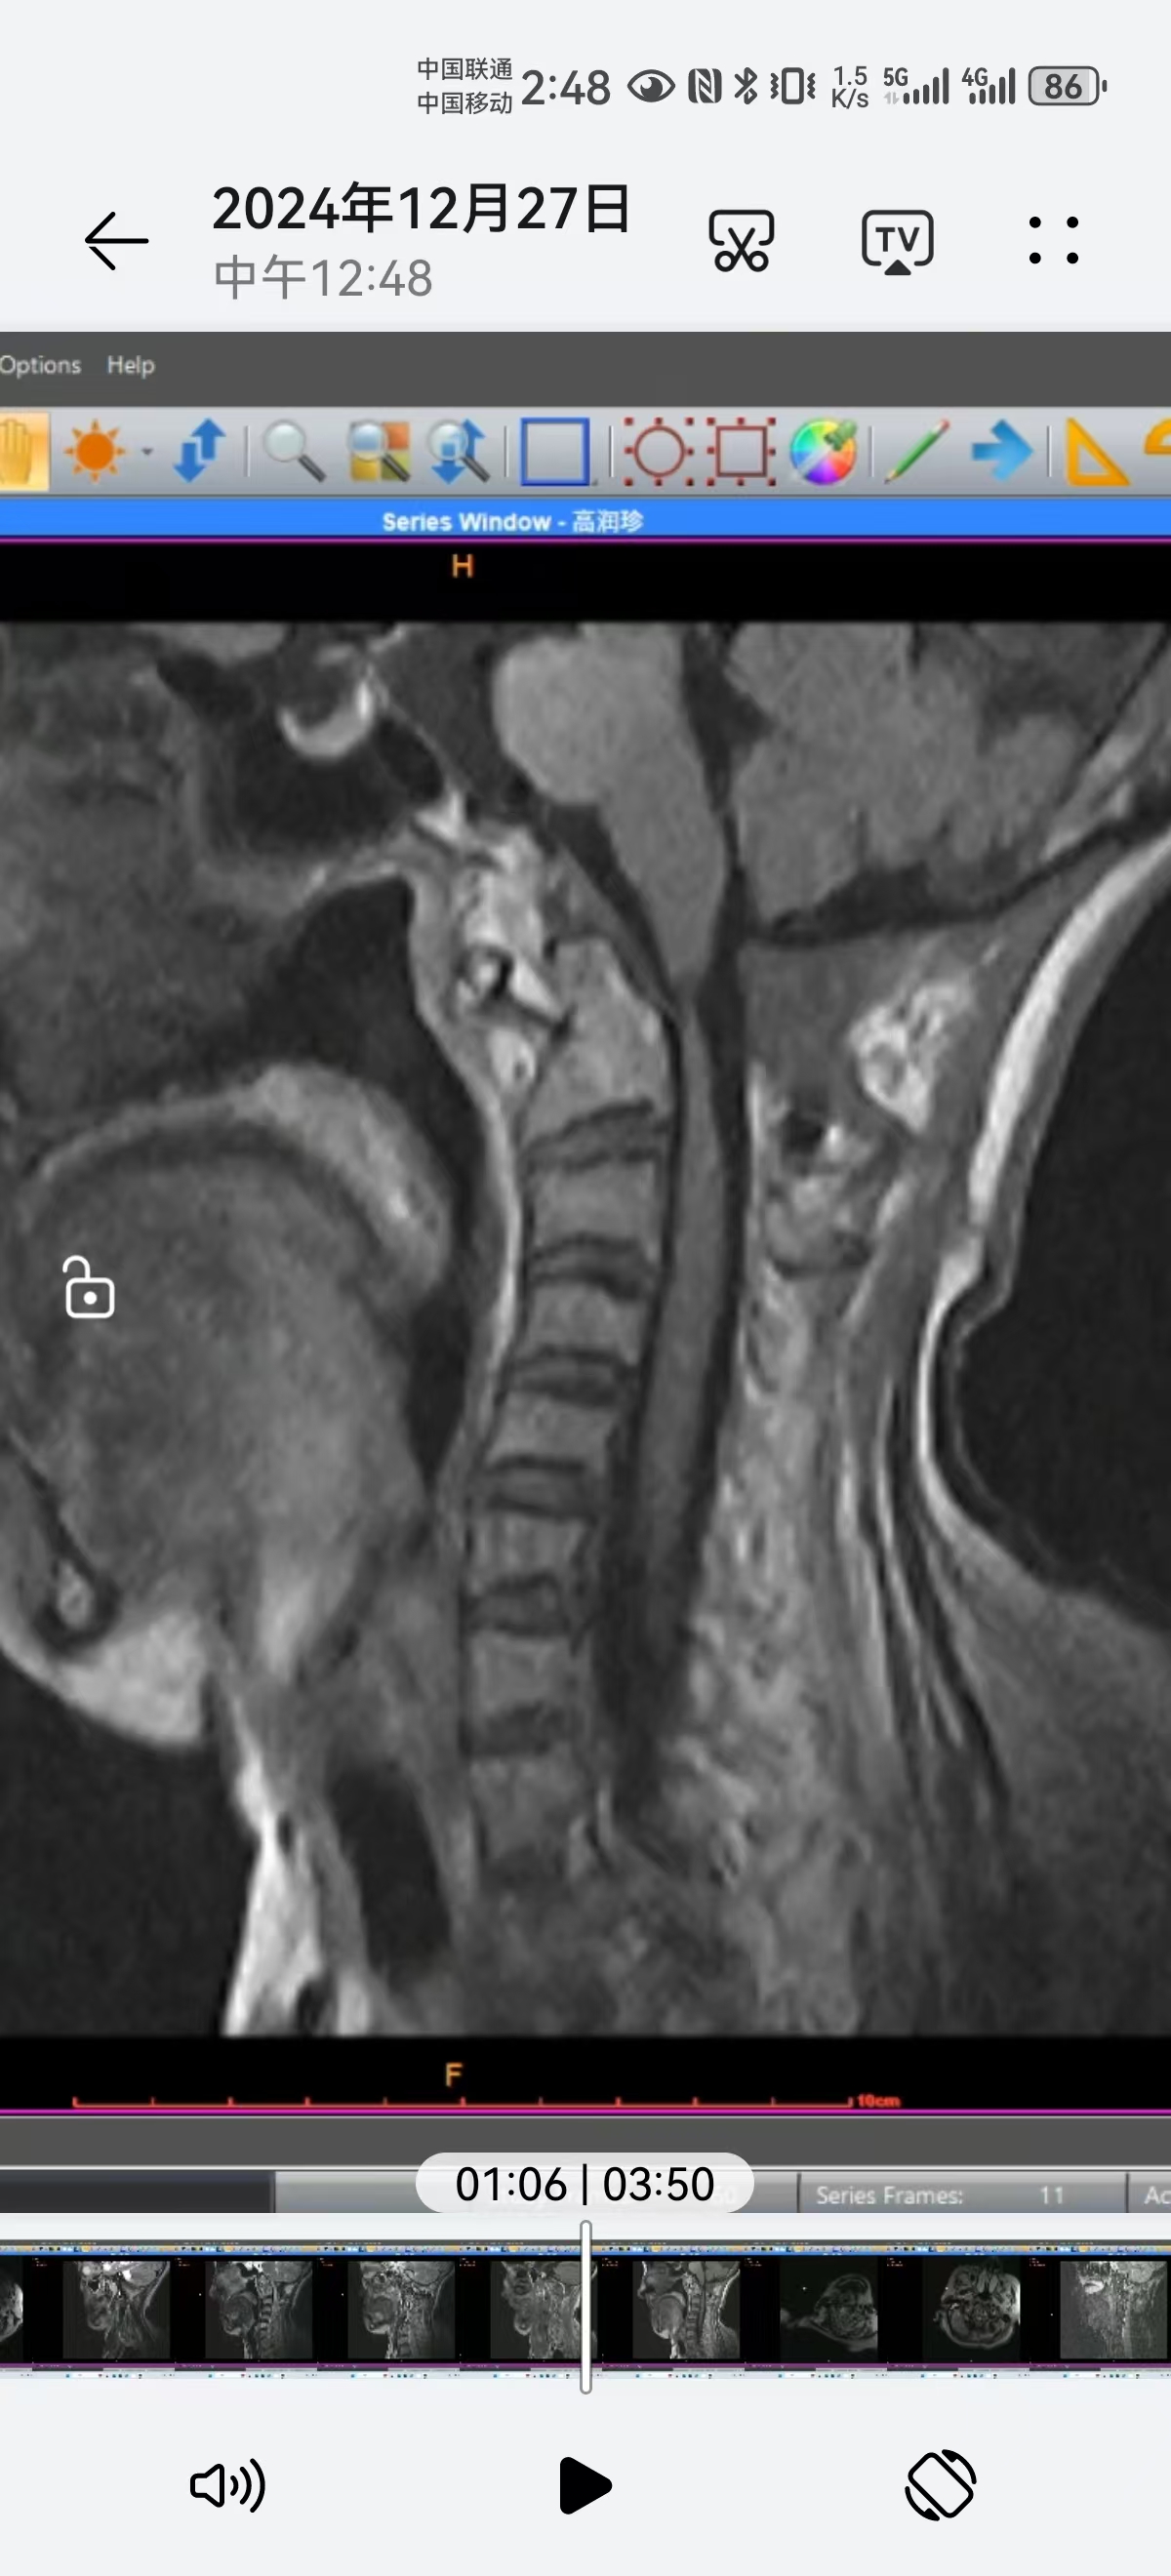

• 术后4个月,在天坛拍0.23低磁场核磁